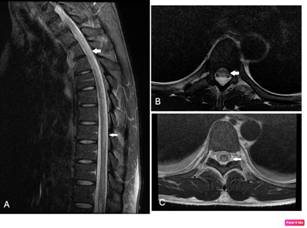

El paciente fue llevado rápidamente al hospital local, que cuenta con cámara de oxígeno hiperbárica, donde iniciaron terapia de recompresión con 30 sesiones, presentando recuperación de la movilidad de los miembros superiores después de la segunda sesión. Dos semanas después del ingreso al hospital local es trasladado a nuestra institución. Se encuentra un paciente en buen estado general, con dolor moderado lumbar y de miembros inferiores, con frecuencia cardiaca 80 por minuto, frecuencia respiratoria de 18 por minuto, tensión arterial de 140/90 mmHg, índice de masa corporal (IMC) de 30.2, con paraplejia flácida con hiperreflexia patelar, dificultad para la micción, estreñimiento y nivel sensitivo T7. En estudio de resonancia magnética (RM) (Siemmens 1.5 Tesla) en nuestra institución de todo el neuroeje, se evidencia hiperintensidad del cordón medular en las secuencias T2, STIR con hipointensidad en T1, de localización central y posterior desde C6 hasta T11 con leve ensanchamiento del diámetro y sin realce al medio de contraste (Imagen 1 y 2). (Figura 1)(Figura 2)

Figura 2 RM de columna torácica en proyección sagital en secuencia STIR (A) con Imagen hiperintensa en cordón medular desde C6 hasta T11. Proyecciones axiales en secuencia T2 que evidencian hiperintensidad medular de localización central y posterior en diferentes niveles () (B y C).